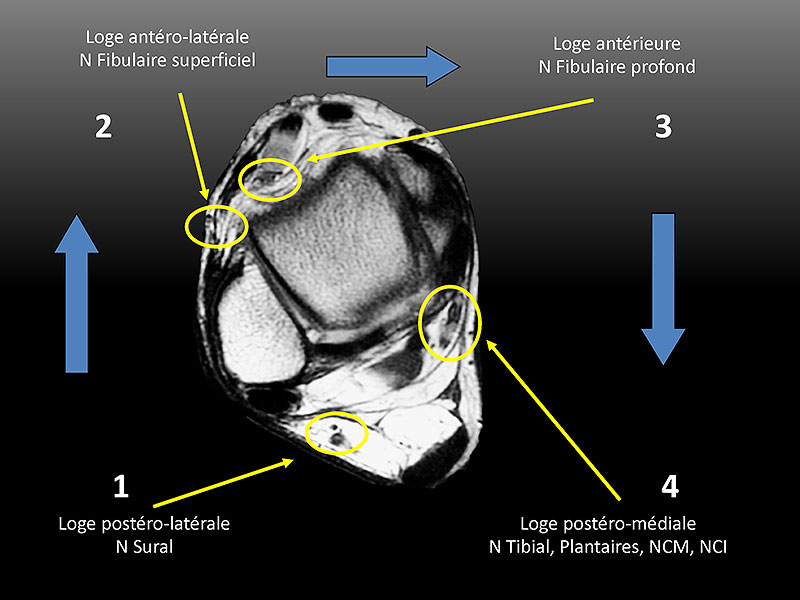

Les nerfs : jambe, cheville et pied

B Bordet, PF Chaillot, A Ponsot, O Fantino